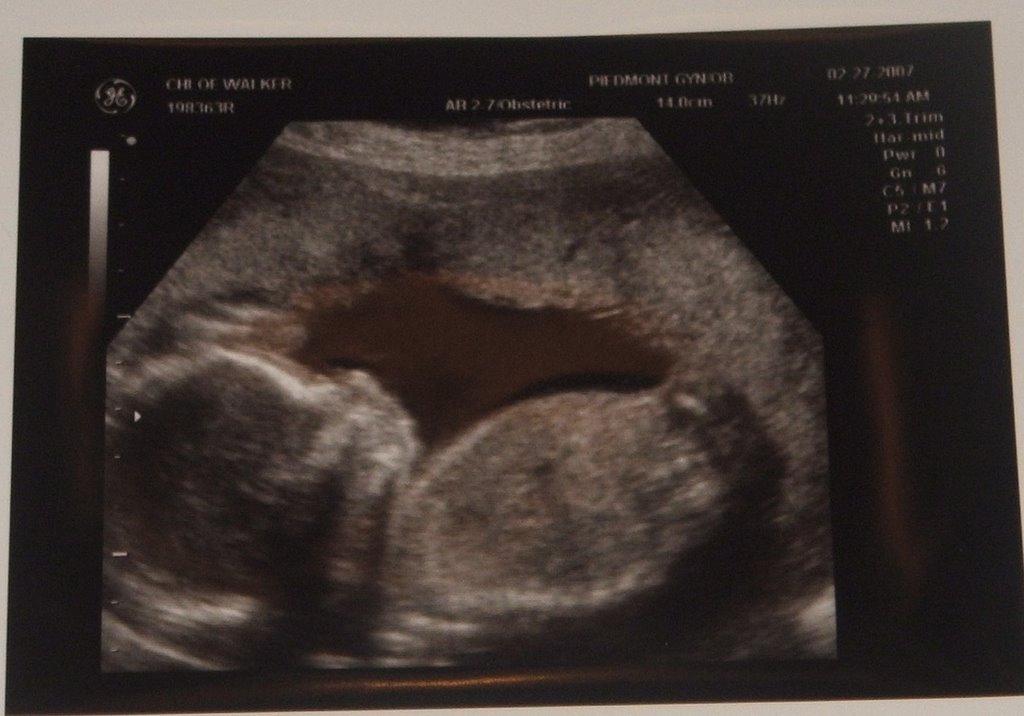

What flavor is it? Why it’s a girl!

And, she has a very chubby tummy. Which the doctor assures me is a good sign and says is more an indication of th QUALITY of foods I’m eating and not so much the QUANTITY I’m eating. Yeah! So…. 20 weeks and counting.